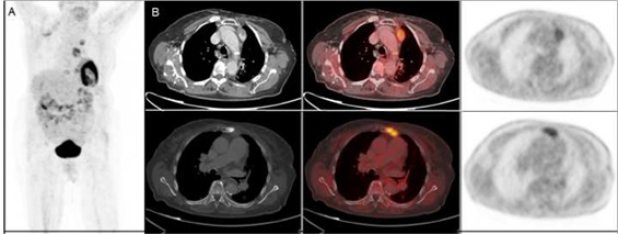

Mujer de 89 años diagnosticada de carcinoma mucinoso de mama izquierda estadio IIB (T2 N1 M0), tratado con cirugía más linfadenectomía axilar. Histológicamente, existía estroma mucoide en el tumor y sustitución masiva metastásica mucosecretora en ganglios axilares. Tras la radioterapia continúa seguimiento con remisión completa. A los seis años presenta elevación del antígeno carcinoembrionario (CEA), astenia y dolor en dorso. Es remitida al Servicio de Medicina Nuclear para descartar afectación ósea secundaria. La gammagrafía con 99mTc-HDP presenta un depósito en el esternón sugerente de malignidad y otro foco paraaórtico izquierdo, de difícil caracterización. El SPECT-TC de tórax localizó correctamente la captación sobre un nódulo mediastinal (fig. 1). Posteriormente, se realizó un PET-TC con 18F-FDG para re-estadificación, evidenciando compromiso metastásico óseo y ganglionar mediastinal (fig. 2).